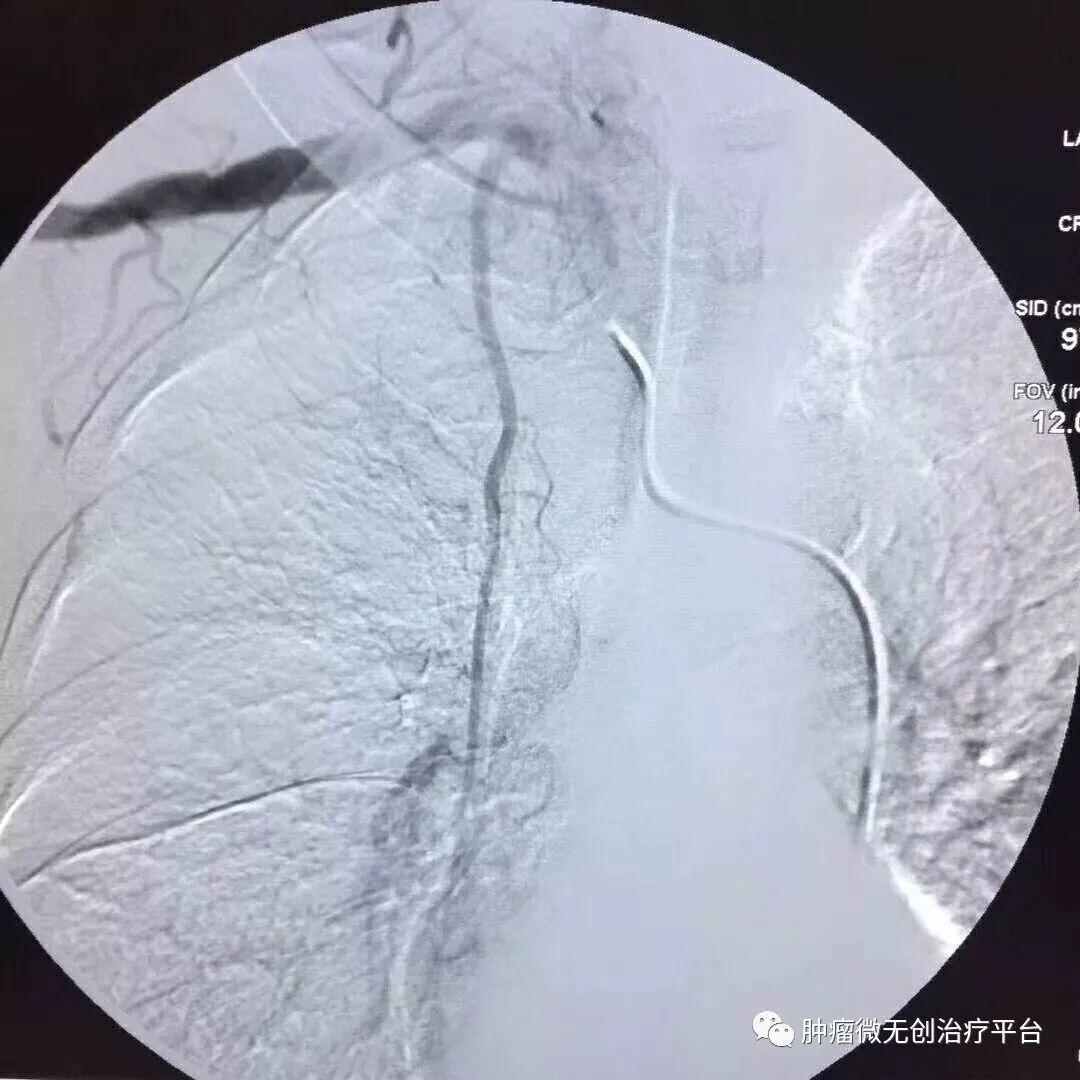

患者情况高龄(79岁)右肺腺癌侵犯胸壁患者肿瘤供血动脉栓塞➕氩氦刀冷冻消融术:图1-2术前PET-CT;图3术前CT;图4-5肿瘤供血动脉栓塞介入;图6-9氩氦刀冷冻消融治疗。